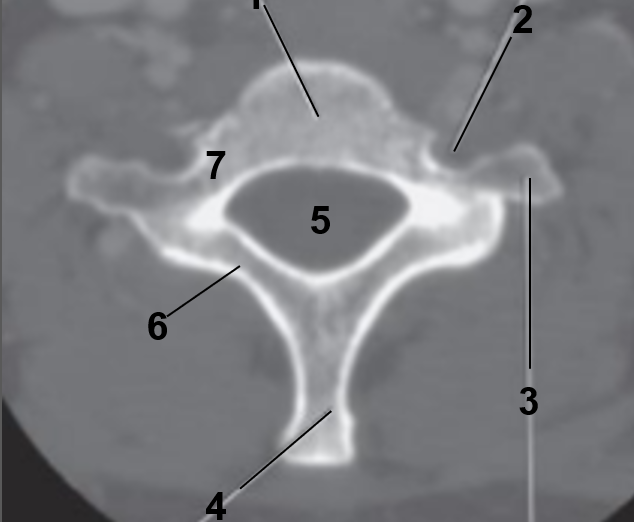

1

Dens

2

Lateral Masses

3

Atlas

4

Atlanto-occipital joint

5

Body of the axis

6

C2-C3 Intervertebral disc

7

C3